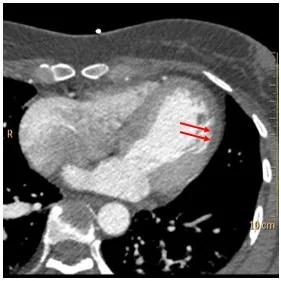

Now look at spectral images. There is clear iodine deficit in the lateral wall. This is well seen on the fusion image. This is an acute MI in the circumflex territory.

Iodine map: No iodine uptake consistent with hypoperfusion

Fused image with iodine overlay: Nice depiction of perfusion deficit